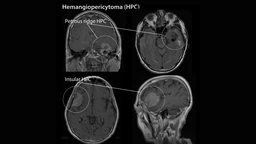

U tế bào quanh mạch là một loại sarcoma mô mềm có nguồn gốc từ các tế bào quanh mạch máu trong thành mao mạch. Khối u này thường gặp nhất ở vùng đầu và cổ. Khi ở bên trong hệ thần kinh, mặc dù không hoàn toàn là u màng não, nhưng đây là khối u có tác động tiêu cực đến não.

U tế bào quanh mạch (Hemangiopericytoma) là các khối u hình thành từ mô mềm và các mạch máu bao quanh mô mềm đó trong cơ thể. Các khối u này có thể xuất hiện ở bất kỳ vị trí nào trong cơ thể có mạch máu, nhưng thường gặp nhất ở vùng đầu và cổ, đặc biệt là tại nền sọ.

U tế bào quanh mạch có thể lành tính (không ung thư) hoặc ác tính (ung thư). Những khối u ác tính có khả năng di căn, chủ yếu đến phổi và xương. Trong trường hợp khối u tế bào quanh mạch nằm ở khoang mũi (glomangiopericytoma) và xoang cạnh mũi, tiên lượng thường tốt hơn vì chúng có xu hướng ít xâm lấn và không di căn.